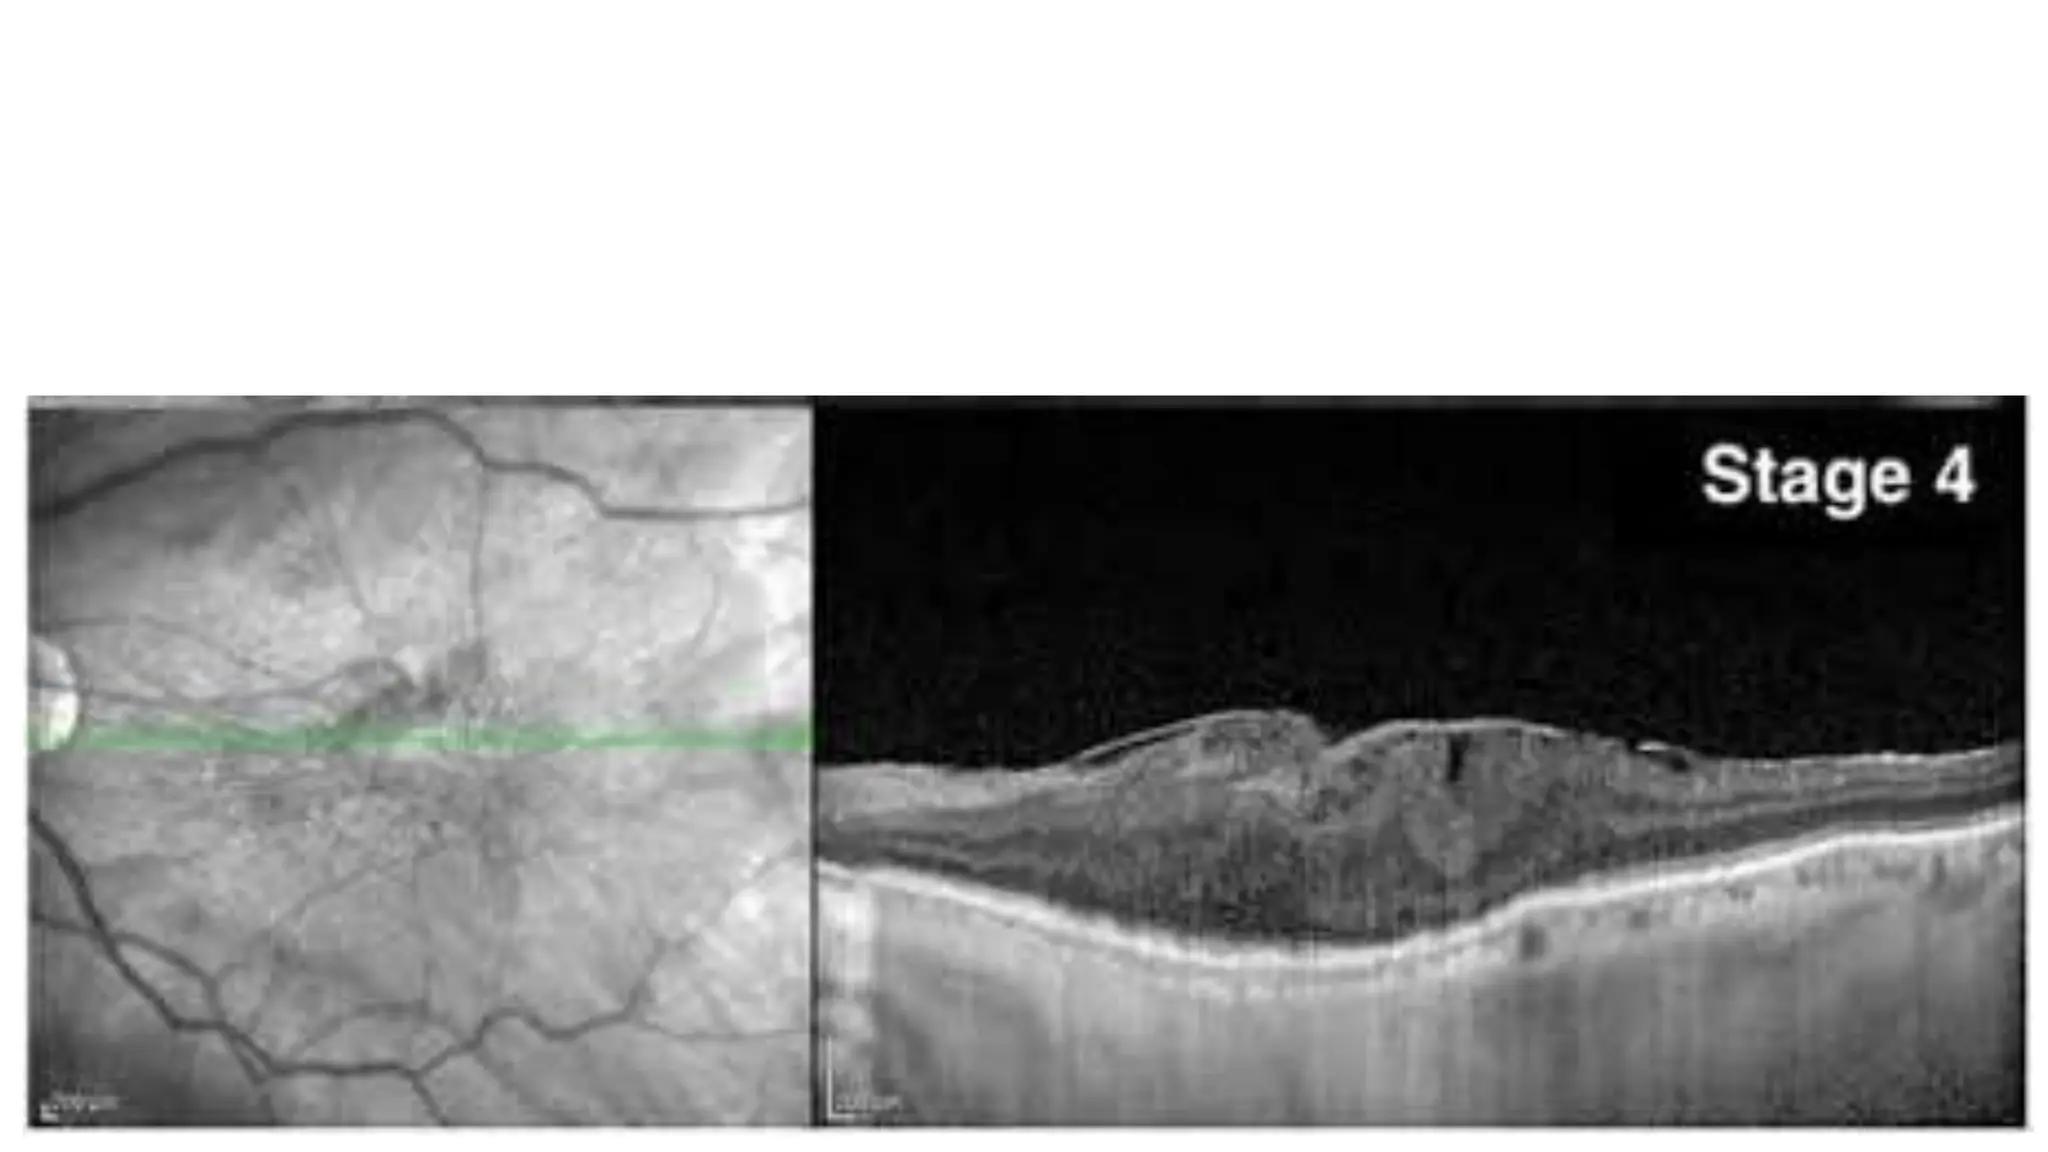

The document discusses various stages of posterior vitreous detachment (PVD) and associated ophthalmological conditions. It highlights the classification of PVD stages, including no PVD, paramacular PVD, and complete PVD, alongside related factors like traction and retinal issues. Key acronyms and terms relevant to diabetic retinopathy and retinal morphology are also mentioned.